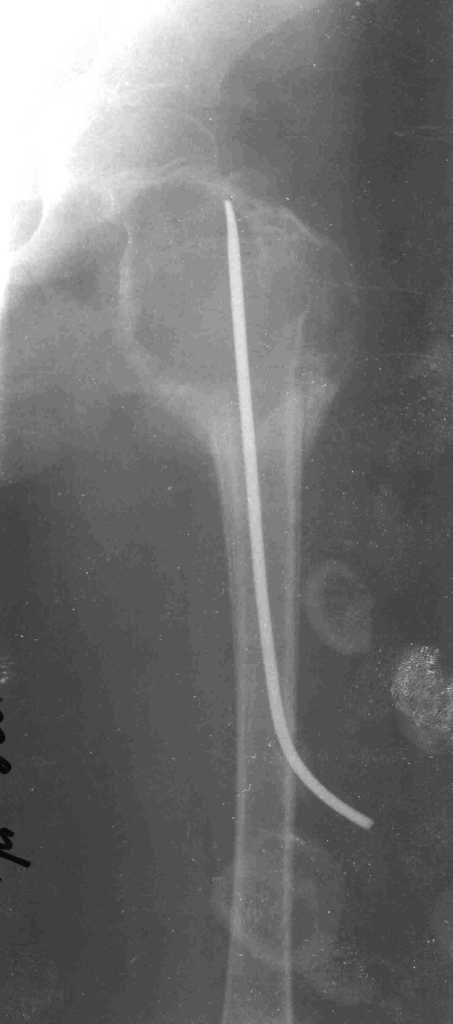

Ребёнок 7 лет. Девочка. Патологический перелом на фоне кисты бедренной кости в ноябре 2007 года.

Скелетное вытяжение. Первичное сращение перелома. После сращения выполнено проведение ТЕN до шейки бедра в надежде на некую стабильность и дренирование кисты в костномозговой канал. На гистологии – типичная картинка для аневризмального процесса. Ребёнок выписан и в апреле 2008 года госпитализирован повторно в связи с прогрессированием аневризмальных изменений на рен.снимках. Двукратное промывание полости гемостатиками под наркозом. Кровь артериальная под давлением 12-15 см.

Повторное в этом году поступление – неделю назад. Резкие боли в области левого бедра после неловкого падения. Срочно госпитализирована. На рентгенограмме – обширное вздутие кортекса проксимального отдела бедра, распространяющееся от физарной зоны до малого вертела. На пункции – артериальная кровь под давлением 14-15 см. Промывание гемостатиками так и не дало чистых вод. Наружный дренаж оставлять опасно.

Течение заболевания практически не оставляет сомнений в необходимости перейти на открытое вмешательство. Вот только сам план операции породил множество версий. Радикальнее всего (и кровавее) – резекция, «семафорная пластика» трансплантатами. Сердце не лежит, так как ели уже рецидивы с полным восстановлением картины через несколько лет у детей в этом возрасте, да и массивно, с кровопотерей превеликой. Красив вариант с кистоскопией артроскопом. Имеется изогнутый каутер, которым, под контролем оптики, можно останавливать кровотечение из сосудов, однако угол зрения оптики и угол полезного действия каутера не безграничны. Больше склоняемся к открытой трепанации кисты. Важнейшим вопросом является – чем и как заполнять полость кисты. Рассматриваются варианты: введение TEN до головки через костномозговой канал, цементирование фиксатора у верхнего и нижнего края кисты, заполнение губчатым аллотрансплантатом; тугое заполнение кисты гелем чешской IKVA, с соответствующим гемостазом; последний вариант – коагуляция всего и вся с заполнением полости гранулами или чипсами. Все эти мысли с оглядкой на неблагоприятно-агрессивное течение процесса в активной кисте. Ошибаться не хочется.